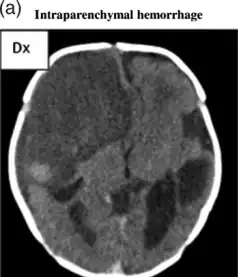

Intraparenchymal hemorrhage

| File:Multiple intraparenchymal hemorrhage.jpg | |

| Multiple intraparenchymal hemorrhage | |

CT scan shows a very large intraparenchymal haemorrhage with mass effect and occupying most of the right frontal lobe

Computed tomography (CT scan): A CT scan may be normal if it is done soon after the onset of symptoms. A CT scan is the best test to look for bleeding in or around your brain. In some hospitals, a perfusion CT scan may be done to see where the blood is flowing and not flowing in your brain.